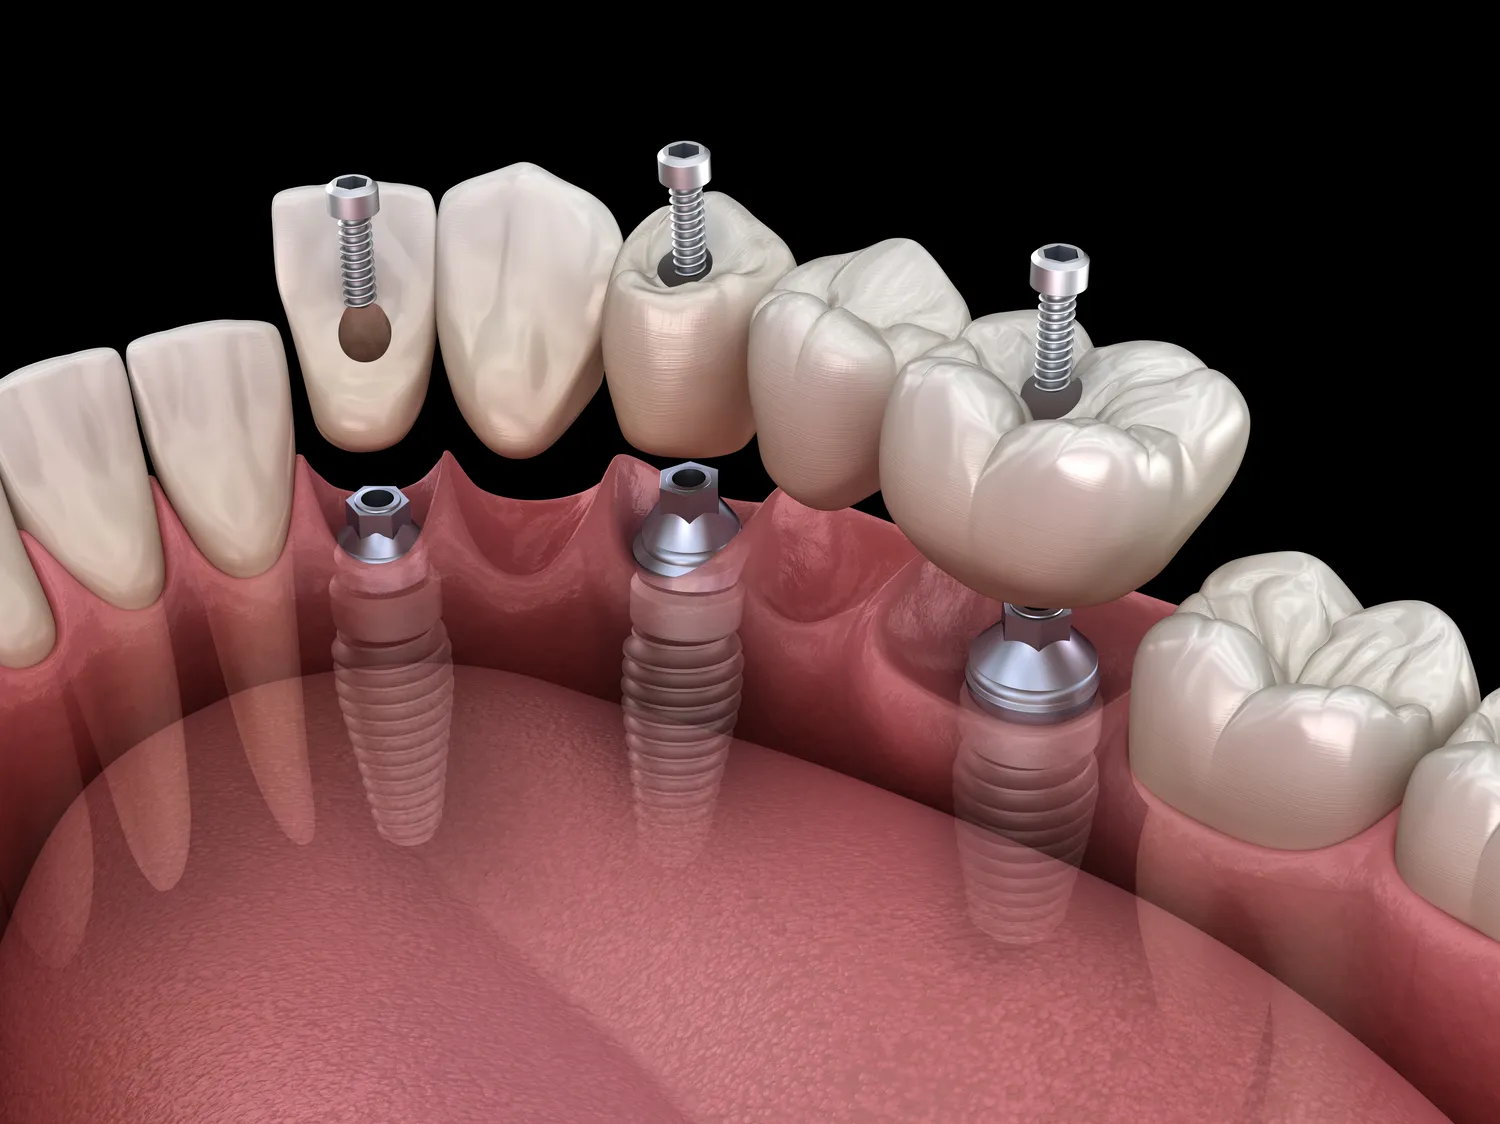

Implanty zębowe to nowoczesne rozwiązanie, które pozwala na odbudowę brakujących zębów. Wśród różnych rodzajów implantów zębowych wyróżniamy kilka podstawowych typów, które różnią się materiałem, kształtem oraz sposobem osadzenia. Najpopularniejsze są implanty tytanowe, które charakteryzują się wysoką biokompatybilnością i trwałością. Tytan jest materiałem, który dobrze integruje się z kością, co sprawia, że implanty te są niezwykle stabilne. Innym rodzajem są implanty ceramiczne, które cieszą się rosnącą popularnością ze względu na estetykę oraz mniejsze ryzyko alergii. Są one szczególnie polecane dla pacjentów, którzy mają uczulenie na metale. Warto również wspomnieć o implantach miniaturowych, które są stosowane w przypadkach, gdy nie ma wystarczającej ilości kości do osadzenia standardowego implantu. Mini implanty są mniejsze i łatwiejsze w zakładaniu, co czyni je idealnym rozwiązaniem dla osób starszych lub tych z ograniczoną zdolnością do przeprowadzania skomplikowanych zabiegów chirurgicznych.

Proces zakupu i wszczepienia implantów zębowych jest skomplikowanym przedsięwzięciem wymagającym starannego planowania oraz współpracy między pacjentem a lekarzem stomatologiem. Na początku pacjent powinien udać się na konsultację, podczas której lekarz oceni stan zdrowia jamy ustnej oraz przeprowadzi badania diagnostyczne takie jak zdjęcia rentgenowskie czy tomografia komputerowa. Na podstawie tych informacji lekarz będzie mógł zaproponować odpowiedni typ implantu oraz zaplanować cały proces leczenia. Po zaakceptowaniu planu przez pacjenta następuje etap przygotowawczy, który może obejmować zabiegi takie jak regeneracja kości czy usunięcie resztek zębów. Właściwe wszczepienie implantu odbywa się zazwyczaj w warunkach ambulatoryjnych i polega na umieszczeniu tytanowego lub ceramicznego korpusu w kości szczęki lub żuchwy. Po tym etapie następuje czas gojenia, który może trwać od kilku tygodni do kilku miesięcy w zależności od indywidualnych predyspozycji pacjenta oraz wybranego rodzaju implantu.